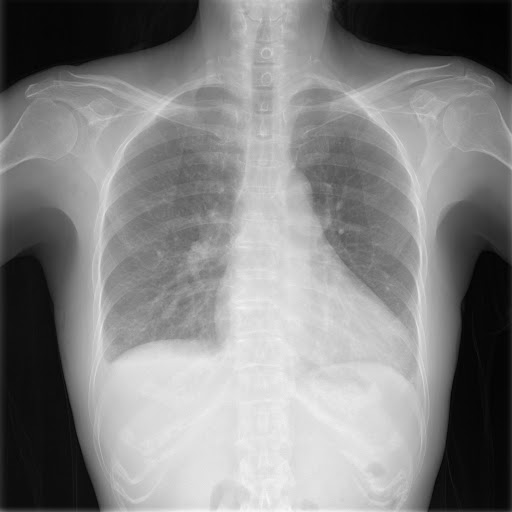

Your values are 16-bit and need to be reduced to 8-bit for display. You can scale them from their current range of 2,712 (i.e. ims.min()) to 4,328 (i.e. ims.max()) with the following: